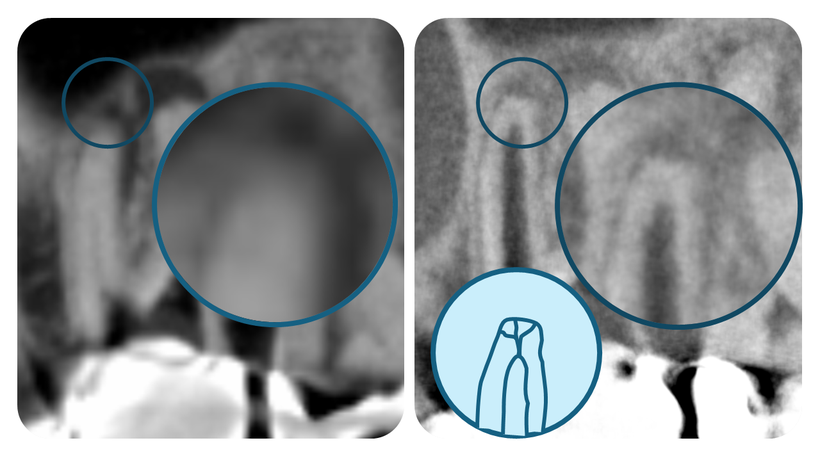

CTの機種によってもこれだけ違う!

下の写真は、左は外注撮影のCT映像、右は後に当院が購入したCTの同部位の映像です。

CTスキャンはメーカーによって解像度が全く異なるのがわかります。